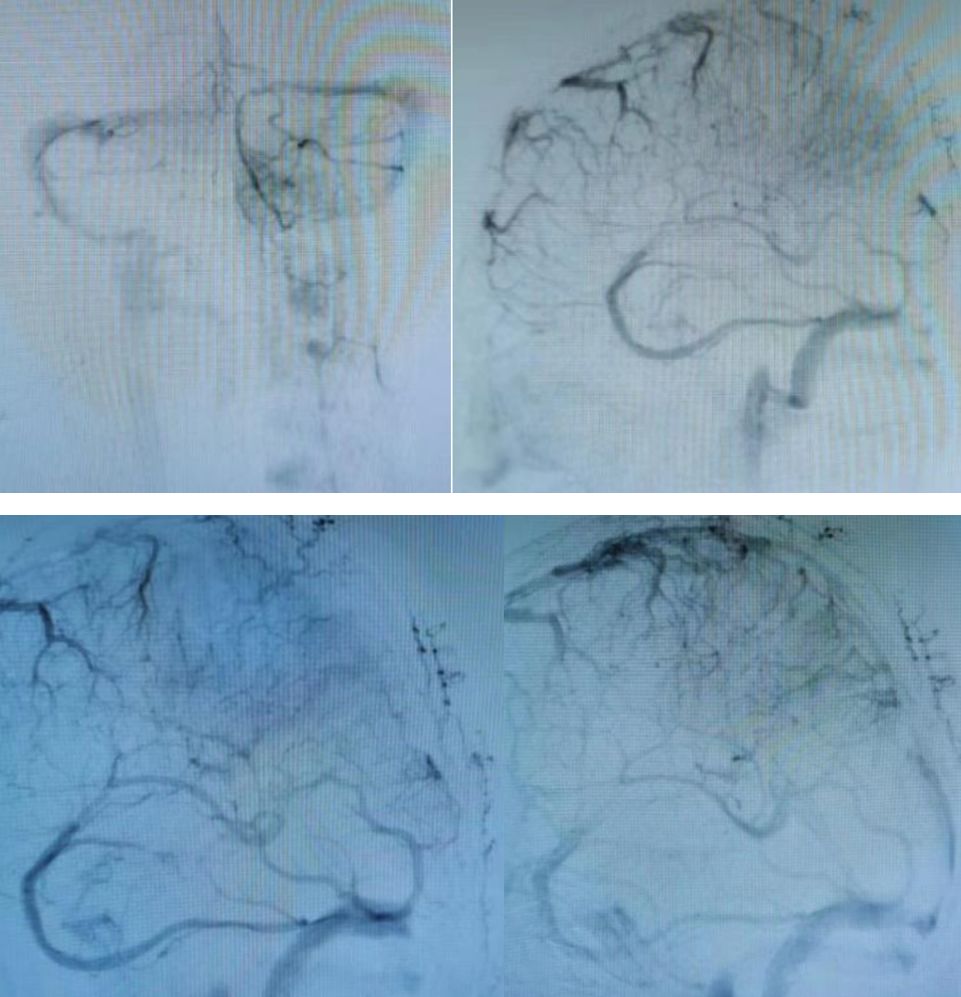

病例3

男性,37岁,头痛4天。既往体健。

答案:右侧额部动静脉瘘。

患者右侧额部血肿破入脑室,患者青年男性,既往体健,非高血压脑出血的常见部位。出血原因考虑动静脉瘘,前交通动脉瘤等。患者增强CT可见增粗的静脉血管影,考虑右侧额部动静脉瘘,患者经过DSA证实,见下图:

答案:上矢状窦血栓,左额叶静脉性梗死。

患者CT示左侧上矢状窦扩张,左侧颞顶叶小片出血,周围水肿,考虑静脉窦血栓,上矢状窦血栓。DSA见下图: